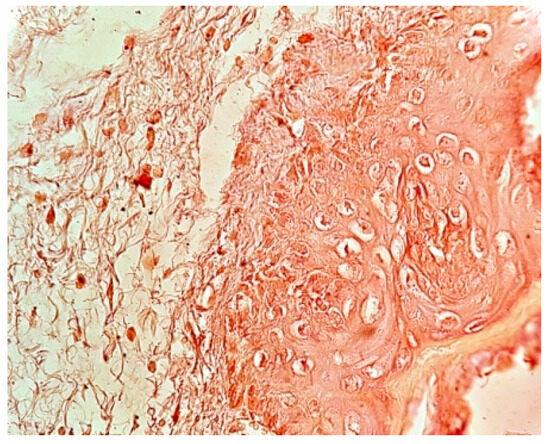

In control group #2 (without rh-BMP injection), 20% of the samples (n = 4) displayed moderate brown staining intensity (Figure 3), whereas 80% of samples (n = 16) exhibited weak brown staining intensity.

Figure 3. View of moderate brown staining intensity in a gingival sample, with bone graft (control group #2) without rh-BMP-2, stained with VEGF antibody. Magnification: 40×.